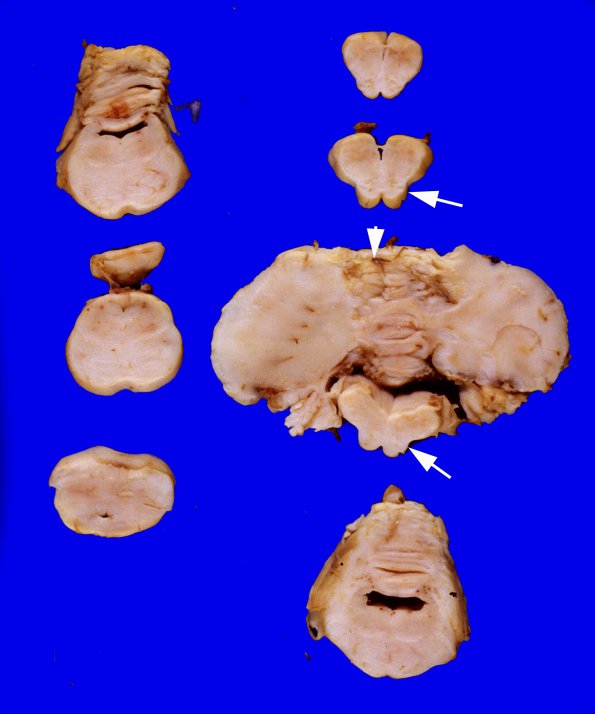

There is marked loss of the contours of the medulla due to abnormality of the ION (arrows) as well as abnormal shape and pallor of the basis pontis. The vermis appears better preserved (arrowhead).